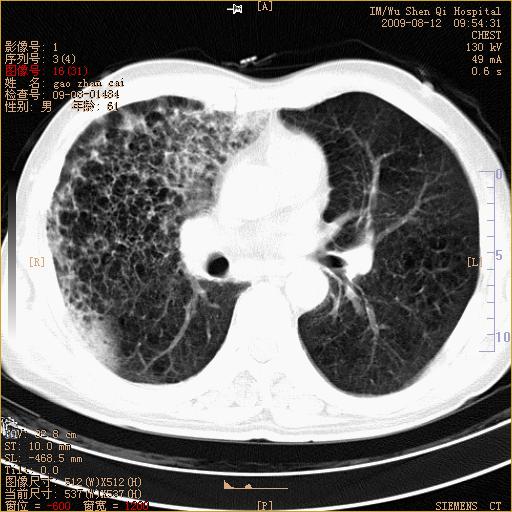

1、右上肺继发性肺结核合并感染;2、肺气肿。

右肺间质纤维化右肺间质性肺炎

右肺上叶干酪性肺炎

右肺弥漫性间质性改变

考虑右肺间质性肺炎并右侧胸膜炎可能性大。

右上肺干酪性肺炎,肺气肿

考虑右肺支扩并感染可能,结核不除外,结核生化检查看看。

右肺间质性肺炎,肺气肿

考虑右肺结核, 右肺间质性改变,肺气肿。

右肺上叶支扩并感染,肺间质纤维化。

1)右肺上叶感染性病变;建议抗炎治疗后复查。2)肺气肿。

右肺上叶支扩并感染,肺间质纤维化,肺气肿,右肺门淋巴结肿大。建议抗炎治疗后复查。